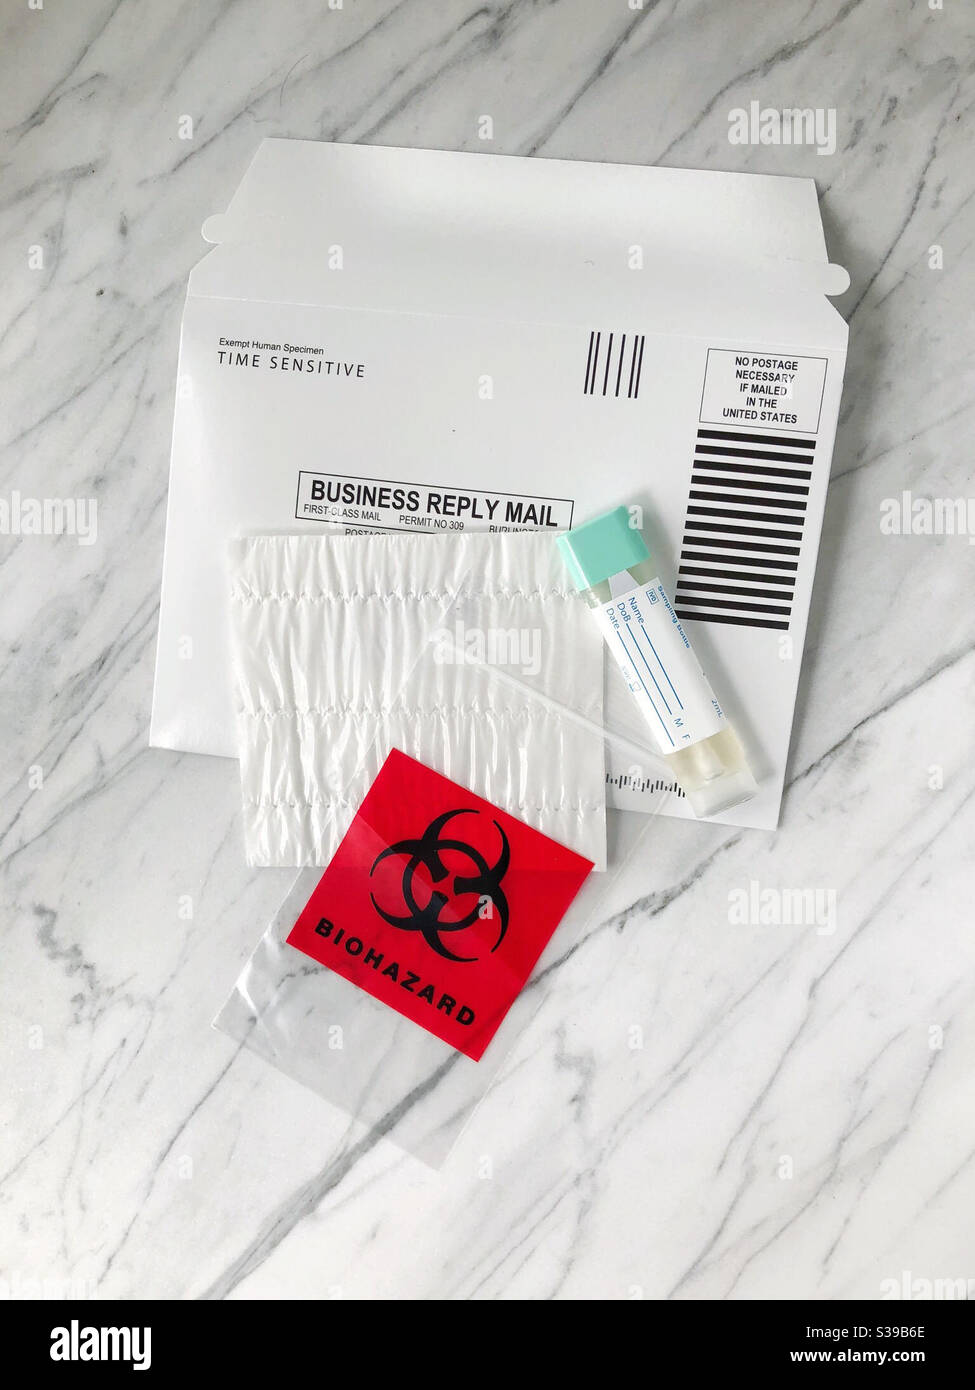

Medical home test kit, mail sample in for testing. Contact free Stock Photohttps://www.alamy.com/image-license-details/?v=1https://www.alamy.com/medical-home-test-kit-mail-sample-in-for-testing-contact-free-image311836966.html

Medical home test kit, mail sample in for testing. Contact free Stock Photohttps://www.alamy.com/image-license-details/?v=1https://www.alamy.com/medical-home-test-kit-mail-sample-in-for-testing-contact-free-image311836966.htmlRMS39B6E–Medical home test kit, mail sample in for testing. Contact free